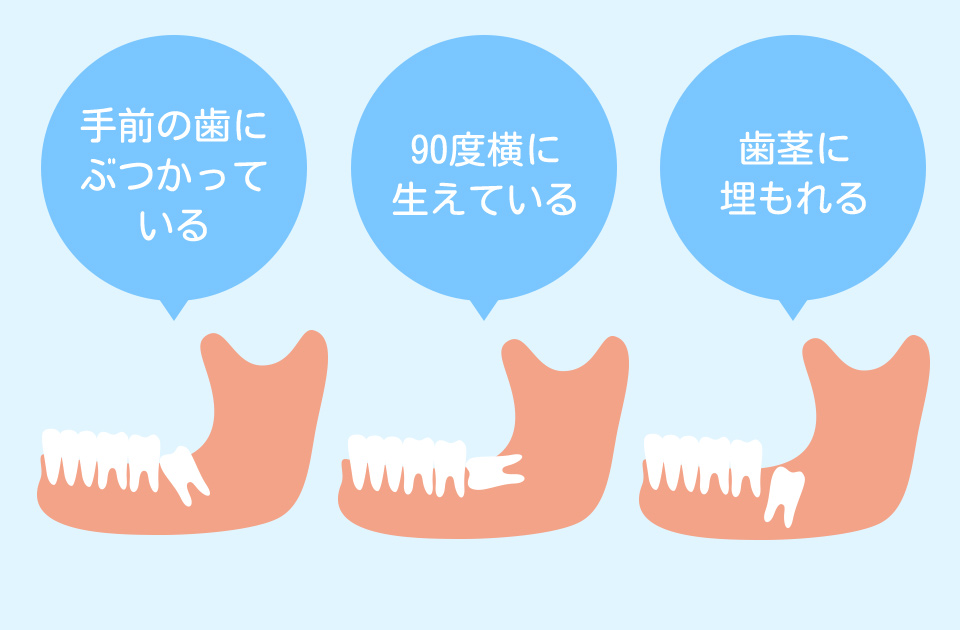

親知らずの抜歯

不要な歯を除去

智歯周囲炎から歯周組織を守る

親知らず(智歯)が正常に生えてこないと、隣の歯とぶつかったり、中途半端に歯肉から露出した状態で汚れが溜まってしまったりすることで炎症を起こしてしまいます。そうなる前に、必要に応じて抜歯を行います。